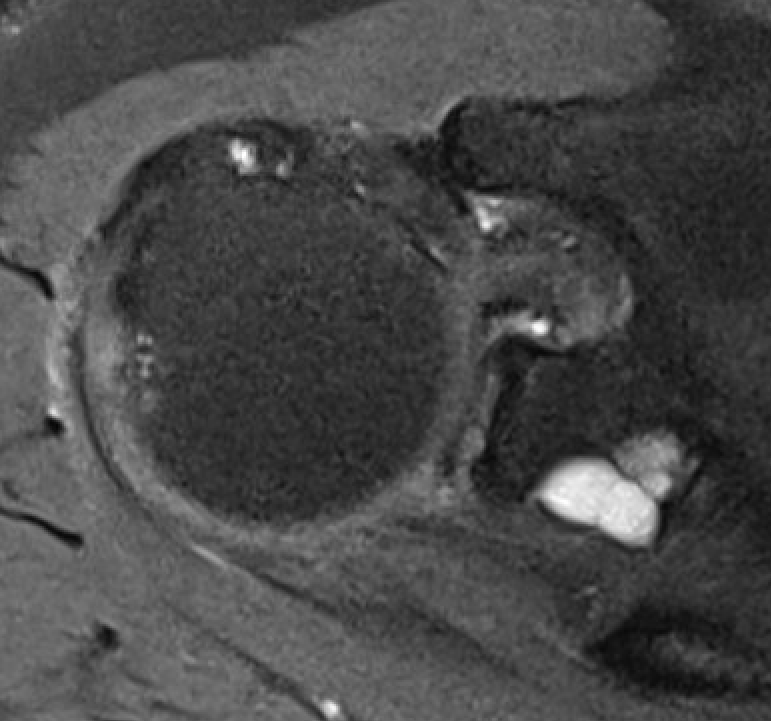

MRI

Spinoglenoid cyst

Spinoglenoid cyst with SLAP tear and posterosuperior labral tear